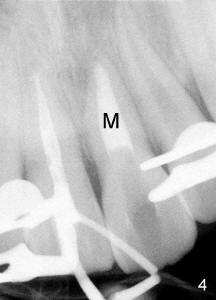

9. Confirm placement of the ProRoot MTA root repair material with a radiograph (Fig.4: M).  If an adequate barrier has not been created, rinse the ProRoot MTA root repair material out of the canal and repeat the procedure